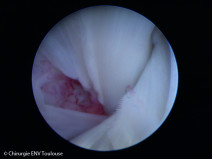

• Formation pratique en endoscopie digestive et respiratoire

La simulation sous toutes ses formes permet d’apprendre et de répéter les gestes ou les actions dans des conditions proches du réel et sans le stress émotionnel.

L’école de Chirurgie de Nancy qui possède un plateau technique dédié d'exception ouvre ses portes aux formations pratiques vétérinaires. L'intervanant, le Dr Patrick Bergeaud, pratique l'endoscopie digestive et respiratoire dep...